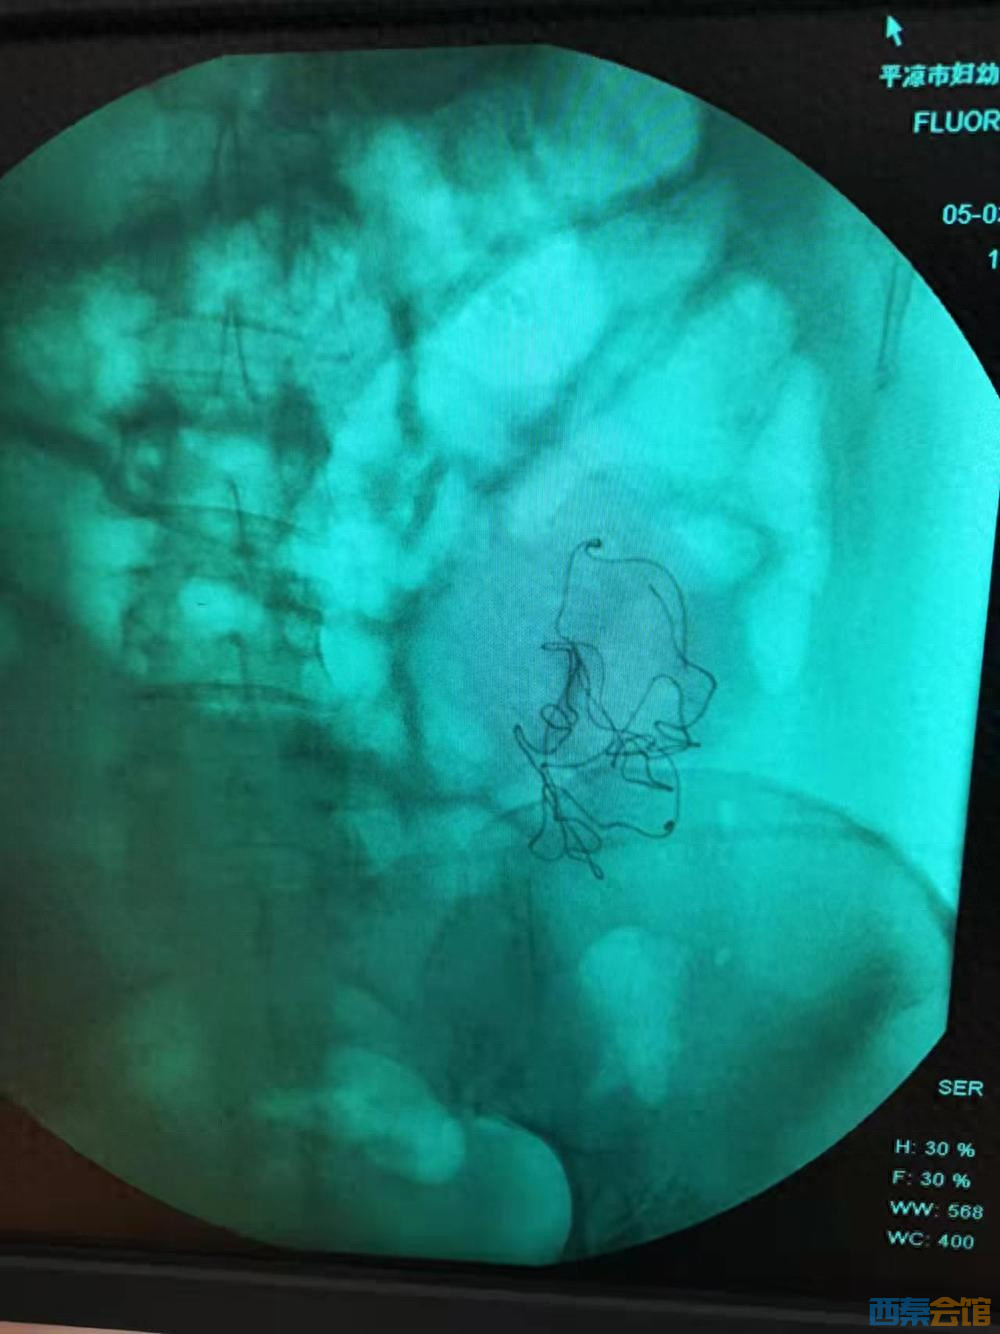

秦红利分娩后,进行X光检查发现异物清晰可见。本文图片均为 受访者供图

当晚 22 时 48 分,秦红利胎膜破裂后出现胎心骤降、脐带脱垂,这一急症若处置不及时,胎儿会快速缺氧窒息。直至 23 时 10 分紧急剖宫产才启动,23 时 23 分女儿佳佳出生,距脐带脱垂已过去 35 分钟。孩子无自主呼吸、口唇发绀,被诊断为重度出生窒息、新生儿缺血缺氧性脑病等,当晚即转至甘肃医学院附属医院抢救。 而秦红利苏醒后,不仅未见到孩子,还目睹医护人员在产房反复寻找遗失纱布,随后被安排 X 光检查,在无医嘱、无签字的情况下被二次开腹。秦红利称,术中清晰看到医生从腹腔取出带血纱布,X 光影像也显示腹腔内有异物影,可院方手术记录却伪造为 “X 线见少量液平面,腹腔渗血止血”。